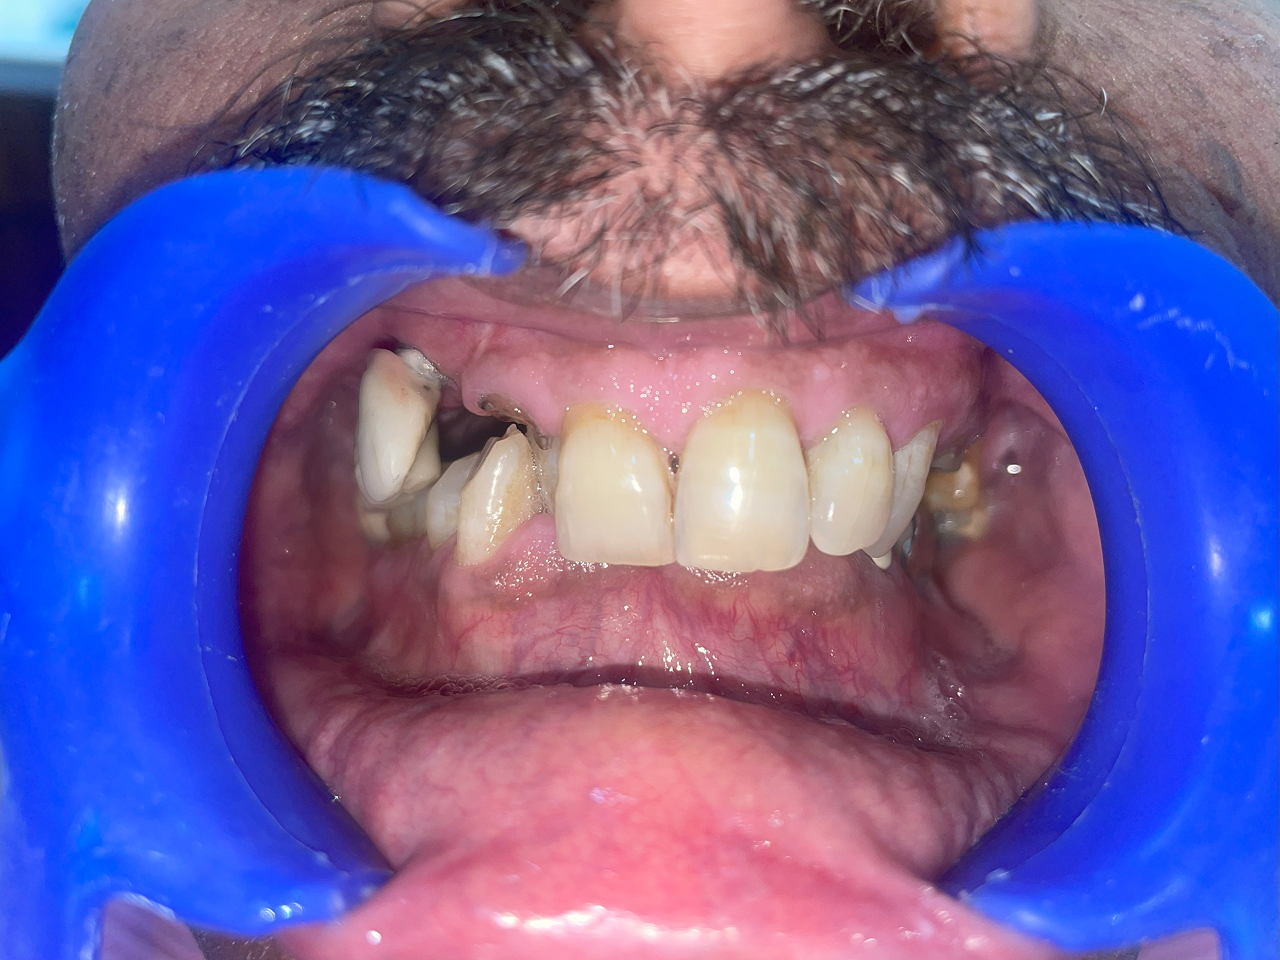

Full Mouth Rehabilitation

This includes comprehensive dental work such as implants, crowns, root canals, and other restorations to fully restore dental health and aesthetics.

Before treatment

Before vs After Treatment Results